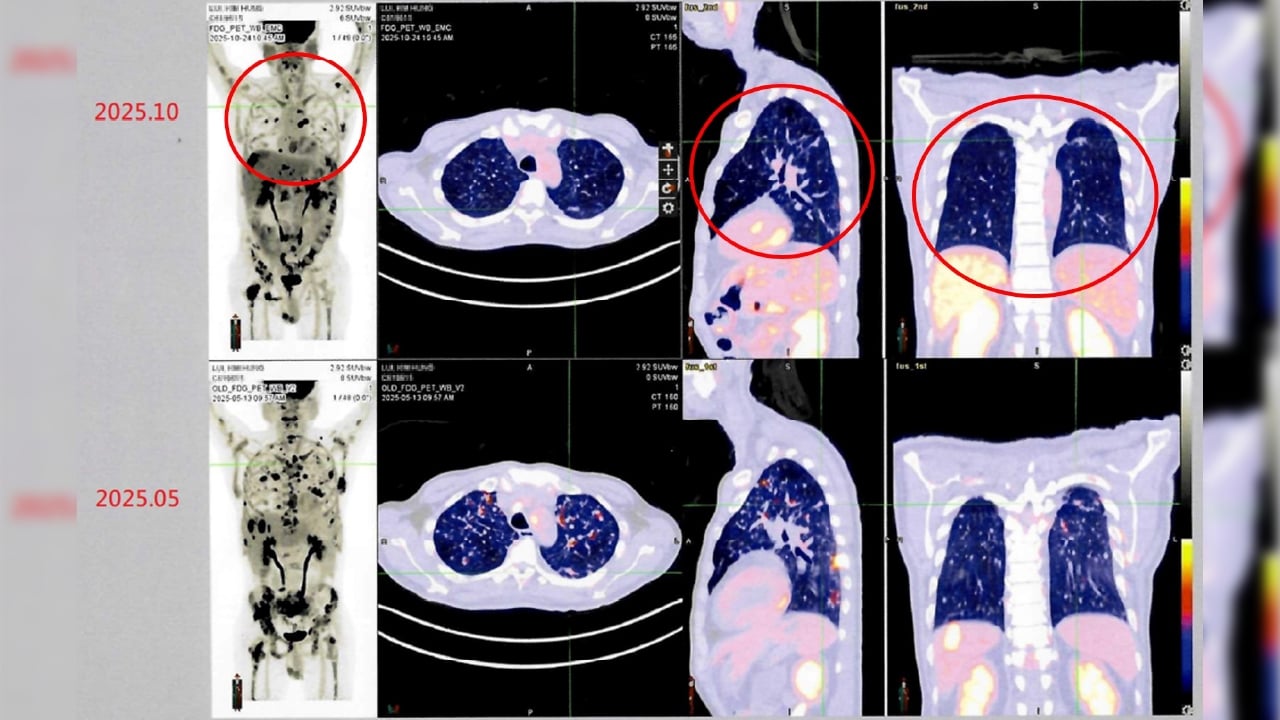

衛生福利部雙和醫院有位來自香港的男性病患(50歲)。他於2024年在香港被診斷出罹患第四期肺癌,歷經多次傳統化療與標靶治療後,為尋求新的治療機會,他評估後決定來台灣進行自體免疫細胞治療(DC-CIK)。經過半年整合療程後,最新影像檢查顯示病情穩定,疼痛症狀明顯獲得緩解,體能與生活品質大幅提升。

↑圖說:病人接受自體免疫細胞治療(DC-CIK)後,從治療前後影像資料對比(紅圈處),可發現癌細胞減少許多,顯示病情穩定。(圖片來源:衛生福利部雙和醫院提供)

莊主任指出:「對於部分晚期癌症患者,DC-CIK治療雖非取代性療法,但能與傳統治療(如化療、標靶或放療)相輔相成,有助提升免疫功能與整體生活品質。我們觀察到,許多接受治療的患者在臨床上都有生活品質改善與病情穩定的情況,顯示免疫細胞療法的潛力與價值。」